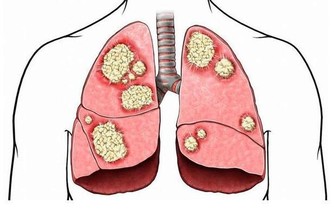

每年單位體檢完,不少男性都會在自己的體檢報告上看見“脂肪肝”三個字。

調查顯示,我國三四十歲的男性中,1/4都患有脂肪肝。脂肪肝大多由酒精中毒和營養過剩引起。男人

事業越做越大,大餐越吃越多,腰圍與日俱增,就“餵養”出了脂肪肝。要想預防,沒什麼“特效藥”

,最關鍵就是每頓吃到七八分飽,尤其是晚飯,千萬別撐著。不僅要少吃紅肉、油炸食品和甜食,少喝酒,主食也不能吃太多,因為饅頭米飯也能轉化成脂肪,進入肝臟。